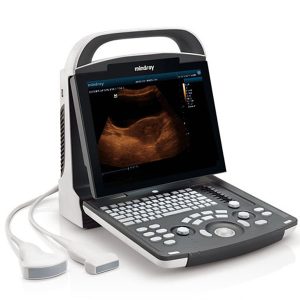

Portable Ultrasound Device Mindray DP 15 Power

250,000.00৳ Add to cartRated 0 out of 5 -